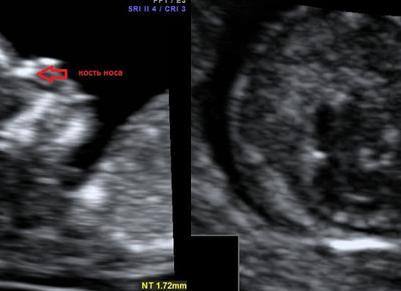

В качестве примера приведем несколько примеров: 1. Ниже на УЗИ мы видим нормальную носовую кость. Можно различить 3 четкие линии.

2. Гипоплазия носовой кости. УЗИ сделано на 12 неделе беременности. Длина – 1,4 мм (ниже границы нормы).